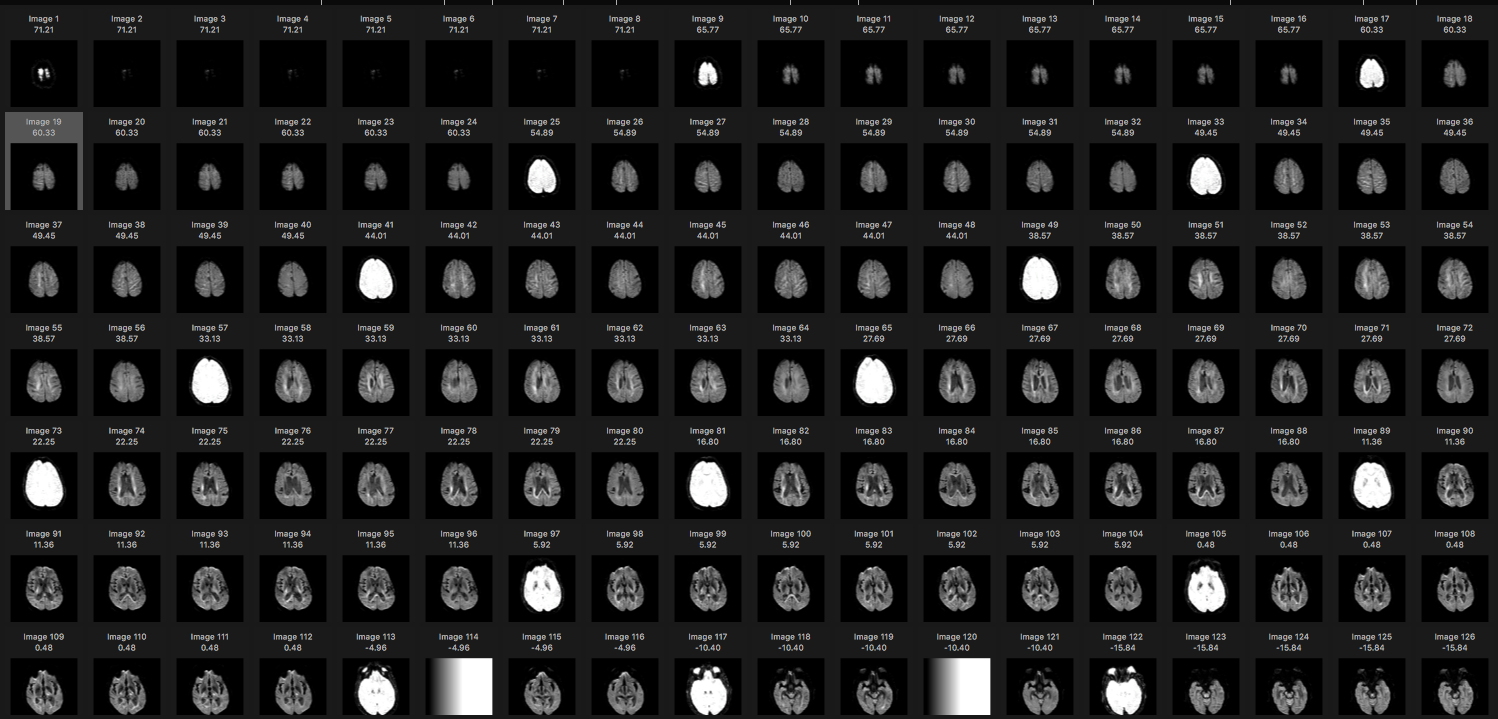

| + | [[File:DWI NEW NOGOP 1.jpg| 320px center|MRI scan series from DICOM folder generated by Osirix software]] | ||

A description of the workflow to produce the medical image rendered in X3DOM here, from the CD containing results of MRI scans.

- Osirix-Lite : This free demo version of the Osirix software for viewing DICOM image files, for Mac OS. Similar DICOM viewers are available for Windows OS